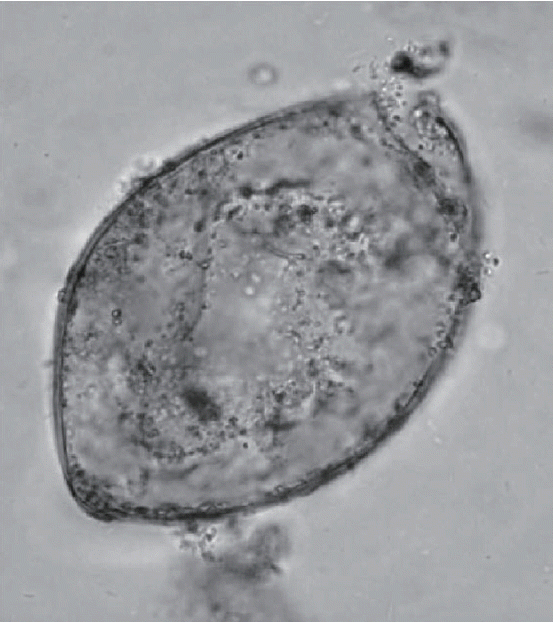

Another ground-breaking aspect of the Peruaçu study was the molecular refinement of microscopic diagnosis of trematode eggs (Fig. 3). Coprolites were present in the mummy and were analyzed by Sianto and her colleagues [19]. Eggs of a common intestinal parasite, hookworm, and an unusual intestinal parasite, Echinostoma spp. were found. Hookworm eggs were relatively rare in this sample, and only 5 were observed. Echinostoma spp. eggs were abundant and numbered 8,300 eggs per gram of coprolite. This suggested that the individual had a true infection. The morphology of the eggs could be described with certainty and were consistent the Echinostoma genus. The species level diagnosis could not be reached with certainty, but the eggs were most consistent with those of Echinostoma luisreyi. Leles and her colleagues [21] showed that the DNA sequence of the ancient eggs was consistent with the species Echinostoma paraensei. Therefore, molecular biology led to a more refined diagnosis at the species level.